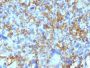

Positive Control

Ramos, Daudi or HuT78 cells. Tonsil or lymph node

Flow (verified)|IF (verified)|IHC, FFPE (verified)|WB (verified)

Flow (verified)|IF (verified)|IHC (FFPE) (verified)|WB (verified)

Higher concentration may be required for direct detection using primary antibody conjugates than for indirect detection with secondary antibody|Immunofluorescence: 0.5-1 ug/mL|Immunohistology formalin-fixed 0.25-0.5 ug/mL|Staining of formalin-fixed tissues is enhanced by boiling tissue sections in 10 mM citrate buffer, pH 6.0, for 10-20 min followed by cooling at RT for 20 minutes|Flow Cytometry 0.5-1 ug/million cells/0.1 mL|Western blotting 0.5-1 ug/mL|Does not react with mouse; others not known|Optimal dilution for a specific application should be determined by user